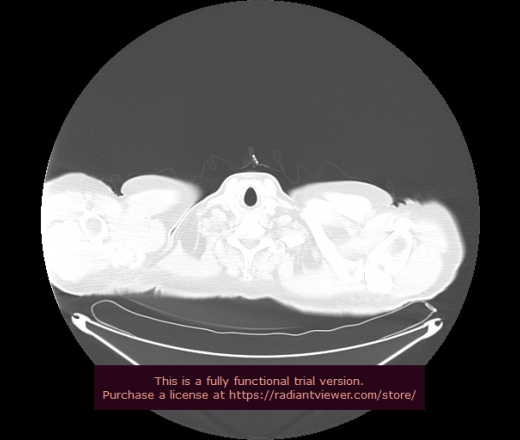

Уважаемые коллеги, если имеется интерес, сможете ли Вы спрогнозировать дальнейшее +-одинаковое течение процесса у 4 данных разных пациентов? Зацепиться где-то можно очень просто, где-то нельзя.